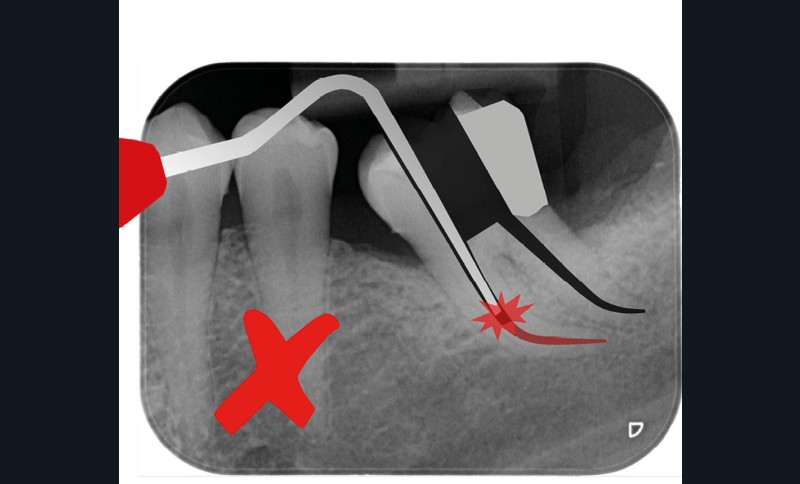

La condensation verticale à chaud est la technique d’obturation de référence. Elle nécessite de compacter la gutta-percha jusqu’à environ LT-4 mm avec un fouloir manuel. Avec les préparations conservatrices, il sera parfois difficile d’atteindre cette longueur, même avec le plus fin des fouloirs. Si on prend par exemple une préparation à 25/.04, le diamètre à LT-4 mm sera de 0,41 mm. Le fouloir le plus fin ayant un diamètre de 0,4 mm, il y a de forts risques de contact latéral avec les parois canalaires s’il atteint LT-4 mm, qui pourrait provoquer un effet de coin. Si le canal est courbe, il sera impossible d’amener le fouloir à la longueur souhaitée (fig. 17).

La condensation latérale à froid impose de pouvoir placer un spreader à LT-2 mm. Avec une préparation plus fine, il sera compliqué d’atteindre cette longueur, notamment s’il y a des courbures. C’est aussi une technique qui génère d’importants stress au niveau radiculaire, exposant la racine à un risque plus élevé de fracture [35]. Avec une préparation préservatrice, il y aura plus de contacts entre le spreader et la paroi dentinaire, et potentiellement une augmentation du risque de fracture (fig. 18).

La thermo-compaction nécessite un instrument rigide, le thermocompacteur, qu’il faut faire travailler à LT-2 ou 3 mm. Le même problème qu’avec les spreaders se posera niveau des canaux courbes. Avec une préparation plus étroite, on aura également plus de risque de contact entre l’instrument en rotation et les parois canalaires. Cela pourrait conduire à un échauffement radiculaire important et de possibles répercussions sur le parodonte en regard [36] (fig. 19).